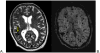

Magnetic resonance imaging scan of a 78-year-old man with CCM1-CHM. Axial T2-weighted image (A) shows a posterior right temporal lobe typical CCM with reticulated, mixed signal internally and peripheral hemosiderin rim (arrow), and a few small additional small foci of low signal. The axial susceptibility-weighted image (B) is more sensitive for blood breakdown products and shows numerous areas of low signal intensity (dark areas on the image) within small CCMs.